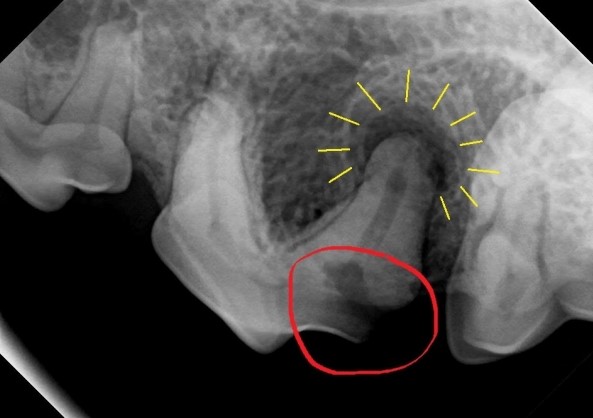

Dental radiograph showing disease below the gumline

Dental Radiographs (X-rays)

Cats: Dental radiographs are required due to the most common feline dental disease—tooth resorption—which occurs below the

gumline and cannot be seen on visual exam.

Dogs: Dental radiographs are strongly recommended to evaluate roots and bone below the gumline. If radiographs are declined for financial reasons, the evaluation below the gumline is more limited.